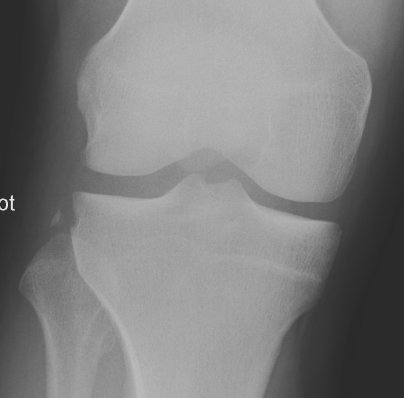

Segond Fracture

This is a very subtle "avulsion fracture of the tibia below the articular margin" caused by traction on the capsular or coronary ligaments. It is not possible to cause this fracture without first rupturing at least one of the major ligaments in the knee.

The classical description1 is limited to the lateral side where associated injuries include:-

The reverse Segond fracture describes similar lesions on the medial side associated with ER+Valgus injuries: -

Examples in order of increasing subtlety: -